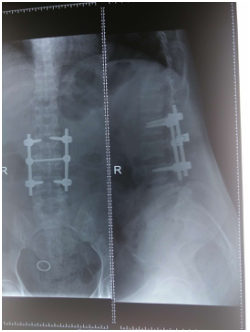

(上圖為患者術(shù)后X片)